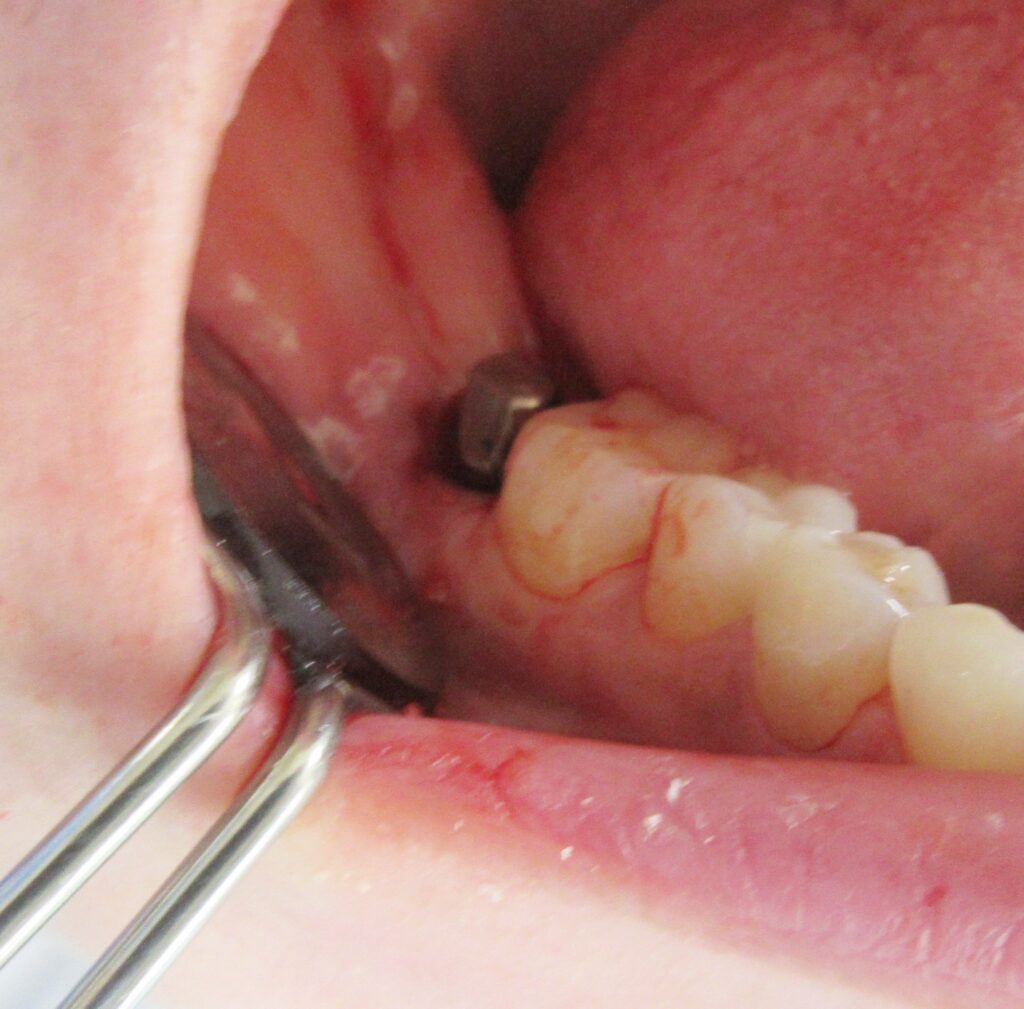

開けた穴に、専用道具を使ってネジを締めるように長さ2センチ程のインプラントを骨に埋め込んでいきます。

しっかりとインプラント埋め込まれた後は、動揺がないか、噛んだ時に当たらないかなどを確認して、最後にパノラマ写真を撮影して今回のオペは終了となりました。